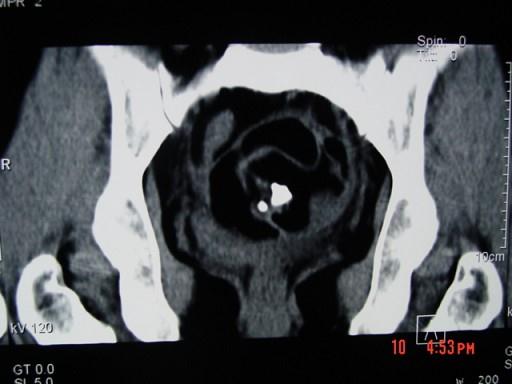

52岁女性患者,因下腹部胀痛就诊,B超提示:盆腔占位,行CT扫描,如图所示盆腔内见囊实性肿块,其内CT值不均,从-120至300hu不等,最可能的诊断为 ...

问题 52岁女性患者,因下腹部胀痛就诊,B超提示:盆腔占位,行CT扫描,如图所示盆腔内见囊实性肿块,其内CT值不均,从-120至300hu不等,最可能的诊断为 ( )

选项 A、卵巢囊肿 B、卵巢粘液瘤 C、盆腔结核 D、子宫肌瘤 E、盆腔畸胎瘤

答案 E